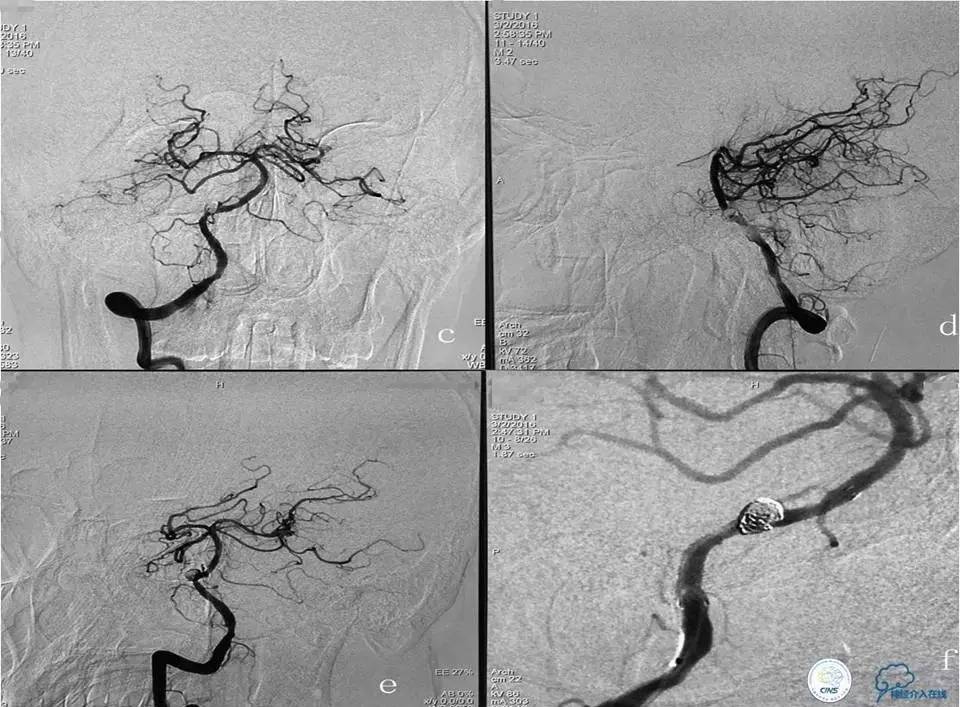

入院后造影检查:

右侧椎动脉正(a)、侧(b)位造影显示右侧椎动脉V4段重度狭窄及右侧椎动脉V4段动脉瘤,狭窄位于瘤颈处,狭窄率为70%,动脉瘤大小为6.99mm×5.95mm,瘤颈宽为3.58mm。

血管内治疗策略:用球囊扩张右侧椎动脉V4段狭窄处,然后采用顺序式操作方式先释放Enterprise支架1枚覆盖瘤颈及支撑血管狭窄处,再结合弹簧圈栓塞动脉瘤。

手术结果如下: